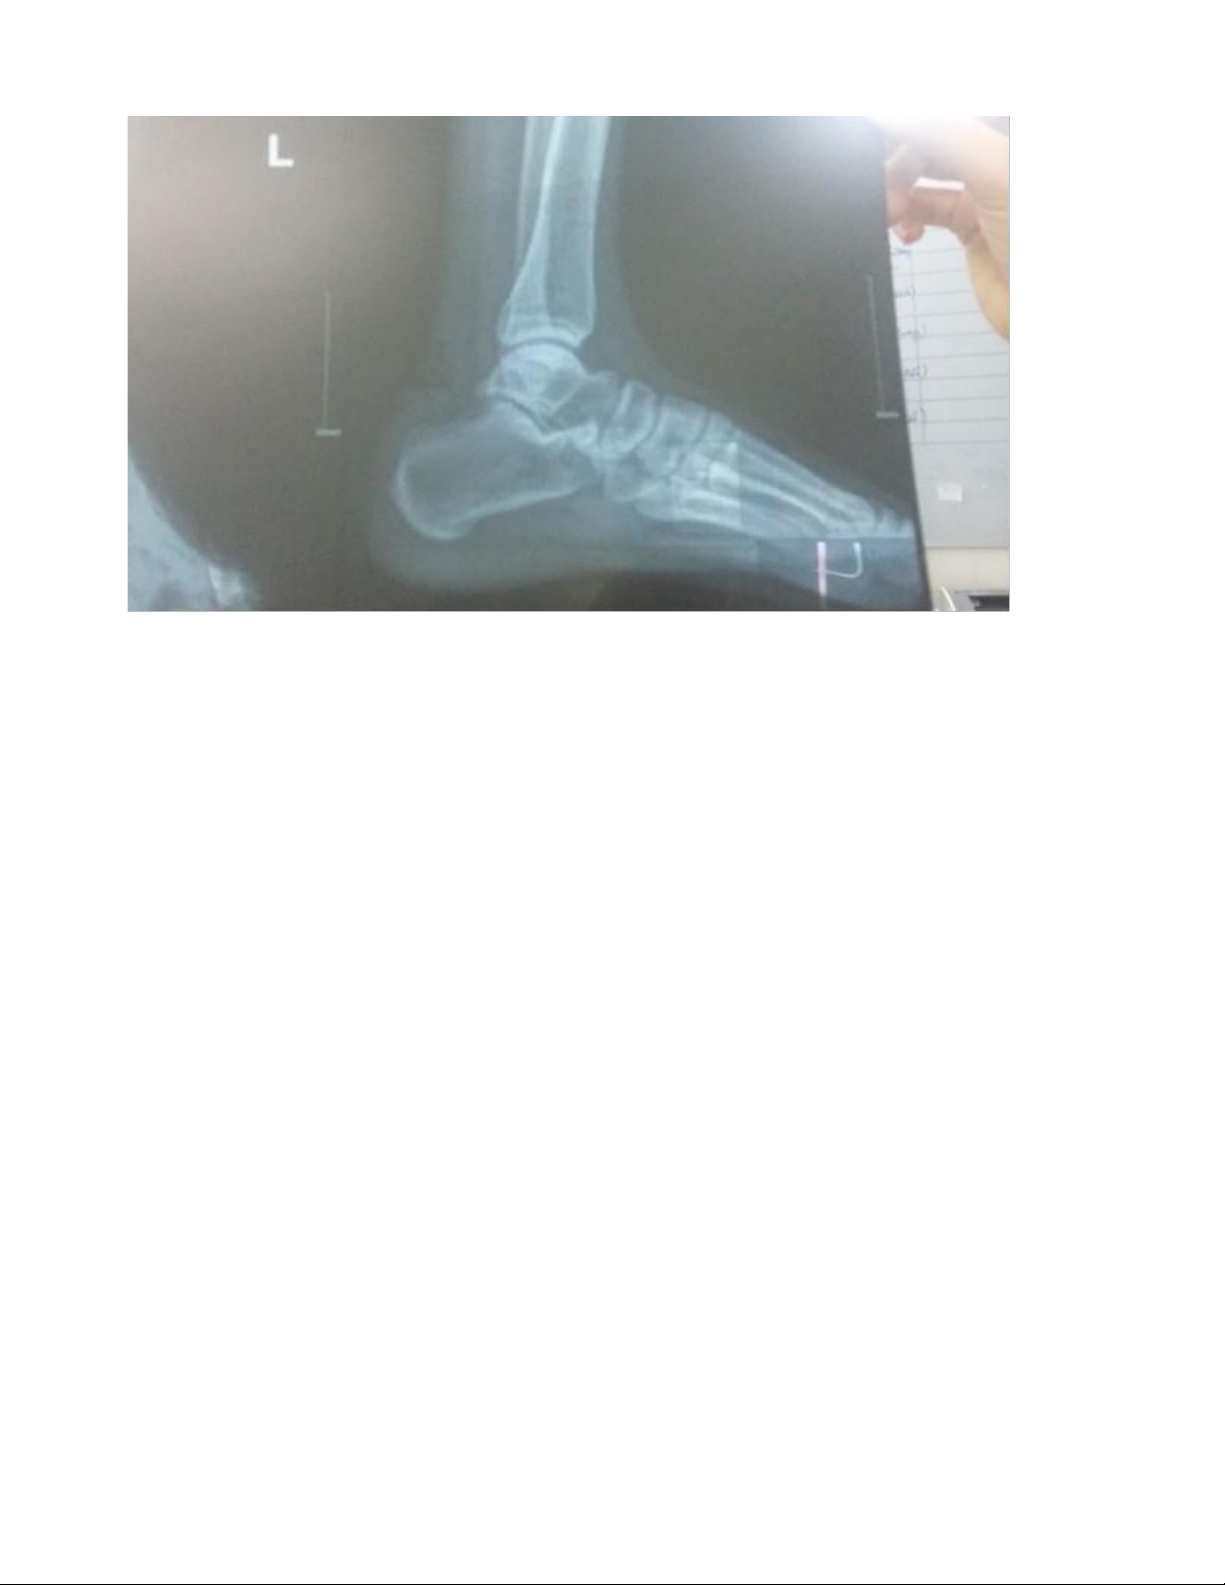

Cận lâm sàng: X quang cẳng chân (Thẳng-nghiêng), X quang ngực thẳng,

Công thức máu, Đường máu mao mạch, HbA1C, Urea, Creatinin, Glucose, Na+ K+ Cl-, ECG, PT, APTT Kết quả cận lâm sàng

- X quang: Chưa ghi nhận tổn thương xương.